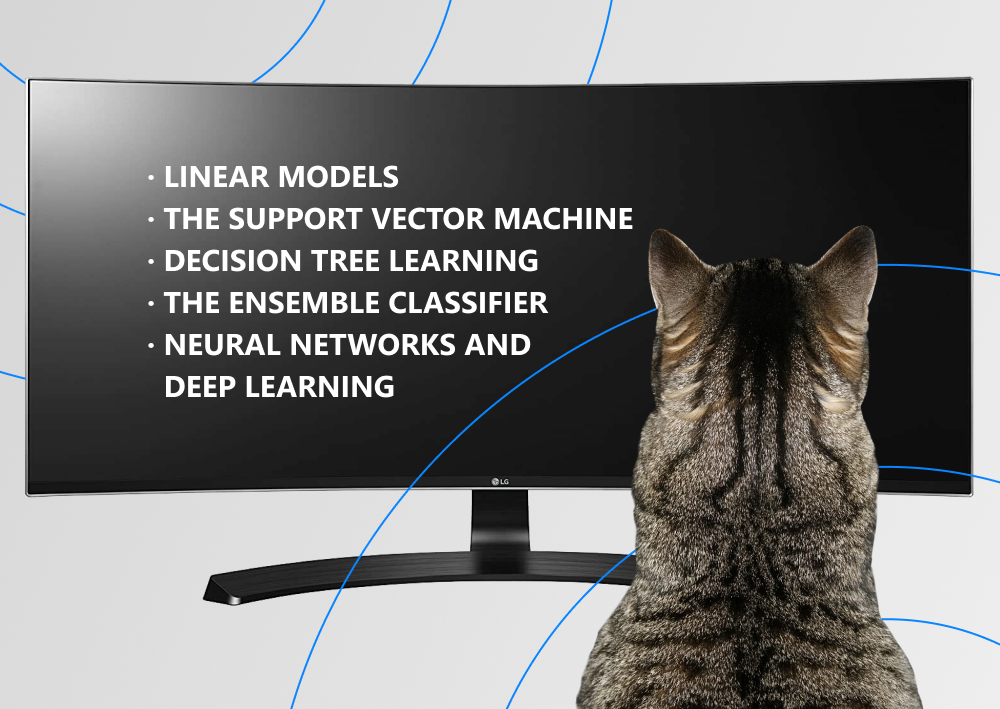

Several machine learning methods have proved their effectiveness for application in radiology:

- linear models are the most common ones for radiology are logistic regression, linear regression, and Fisher's linear discriminant (LDA);

- the support vector machine is a set of kernel-based supervised learning techniques used for regression and classification; it finds an optimum hyperplane for linear separable patterns;

- decision tree learning is one of the top classification approaches in machine learning used for forming random forests for classification and prediction in the analysis of radiological images;

- the ensemble classifier is a combination of multiple classifiers that leads to final classification by bagging and boosting;

- neural networks and deep learning can pick specified features out of the data to detect and classify them.